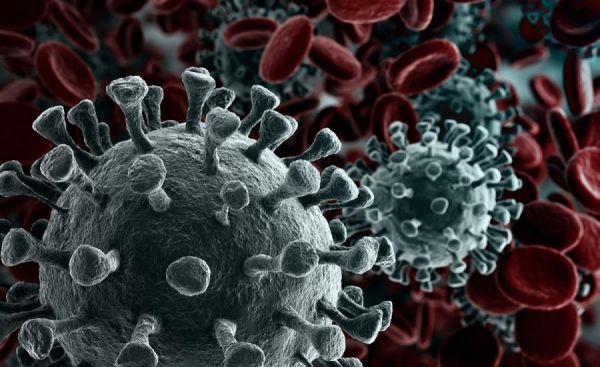

SARS-COV2: Θα τον βρίσκουν οι «κάμερες»;

Η μέτρηση της θερμοκρασίας – με τη βοήθεια ειδικών συσκευών – πλήθους ανθρώπων προκειμένου να εντοπιστούν πιθανοί ασθενείς μπορεί να είναι αξιόπιστη εφόσον ισχύουν κάποιες προϋποθέσεις

Οταν εκεί που περιμένουμε σε κάποια ουρά έρχεται ο αρμόδιος υπάλληλος για να στρέψει το… πιστόλι του προς το μέτωπό μας προσπαθώντας να πάρει τη θερμοκρασία μας, για το καλό όλων βέβαια, ας πάει μια φορά ο νους μας και στον σερ Γουίλιαμ Χέρσελ (1738-1822). Ενας νεαρός μετανάστης ήταν και αυτός της εποχής του. Από το πολιορκούμενο από τους Γάλλους υπό αγγλική κηδεμονία Ανόβερο, όπου γεννήθηκε ως Φρειδερίκος-Βίλχελμ Χέρσελ, έφθασε ως 19χρονος μουσικός σταλμένος από τον πατέρα του στο Λονδίνο. Με σκοπό να προφυλαχθεί από τα δεινά του πολέμου μεταξύ Αγγλίας και Γαλλίας και σε αναζήτηση καλύτερης τύχης.

Μήπως όμως είναι πολύ καλό για να είναι και αληθινό; Και δεν είναι μόνο το πολύ μεγάλο θέμα πως κάποιος μπορεί να είναι φορέας του ιού χωρίς να έχει πυρετό. Υπάρχουν και άλλες δυσκολίες για να ξεχωρίσει μέσα από το πλήθος έστω αυτός που έχει θερμοκρασία πάνω από 37 βαθμούς Κελσίου.

Φαίνεται πως στην καλύτερη περίπτωση όλα αυτά τα «πιστόλια» και οι «κάμερες» θα μπορούν να βρουν κάποιους με πυρετό αλλά όχι να εξασφαλίσουν πως δεν θα κυκλοφορούν μέσα στο πλήθος ενός πολυκαταστήματος και φορείς του οποιουδήποτε ιού.